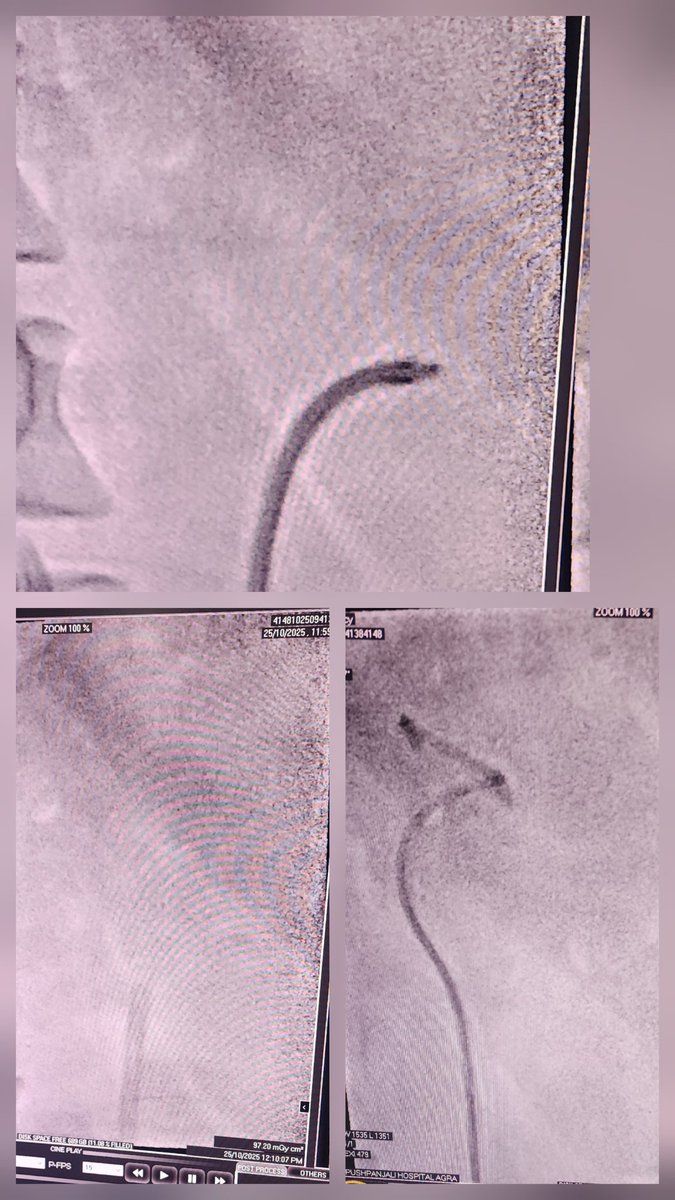

Flexible Ureteroscopy with FANS.. 12 mm stone, 19 min time, complete clearance.. As Good as Suction Mini PCNL. @endouroacademy @usiurolithiasis @sbinhamrii @endouro @OTRAXER @mohamed92902484 @RIRS_inDelhiNCR @DocGauhar @drkarthicknagan @DrParimalGharia